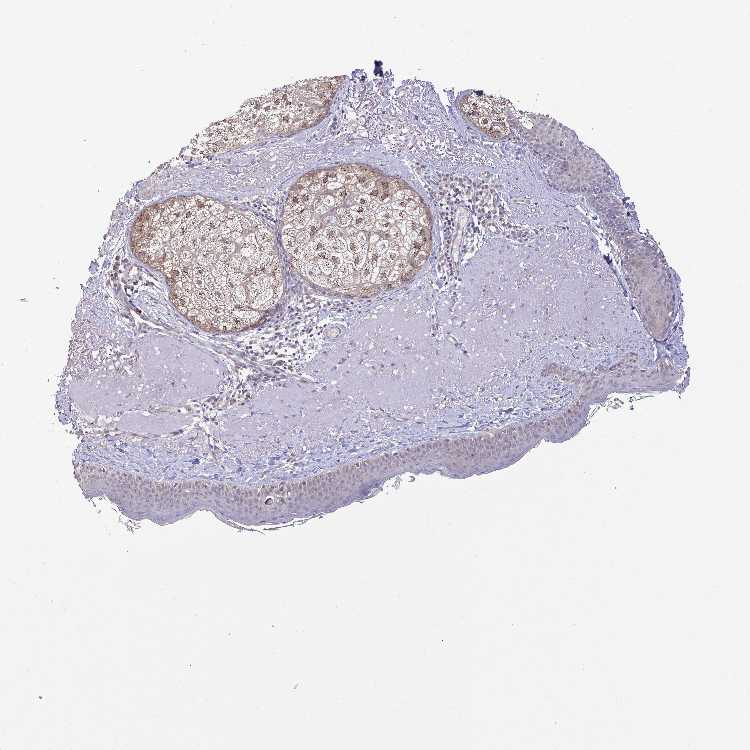

SKIN 1 - Antibody stainingi

Antibody staining in the annotated cell types in the current human tissue is reported as not detected, low, medium, or high, based on conventional immunohistochemistry profiling in selected tissues. This score is based on the combination of the staining intensity and fraction of stained cells.

Each image is clickable and will lead to virtual microscopy that enables deeper exploration of all samples and also displays staining intensity scores, fraction scores and subcellular localization as well as patient and tissue information for each sample.

Antibody HPA052730Antibody HPA056957

Langerhans Not detectedNot detected

Fibroblasts Not detectedNot detected

Keratinocytes Not detectedNot detected

Melanocytes LowNot detected